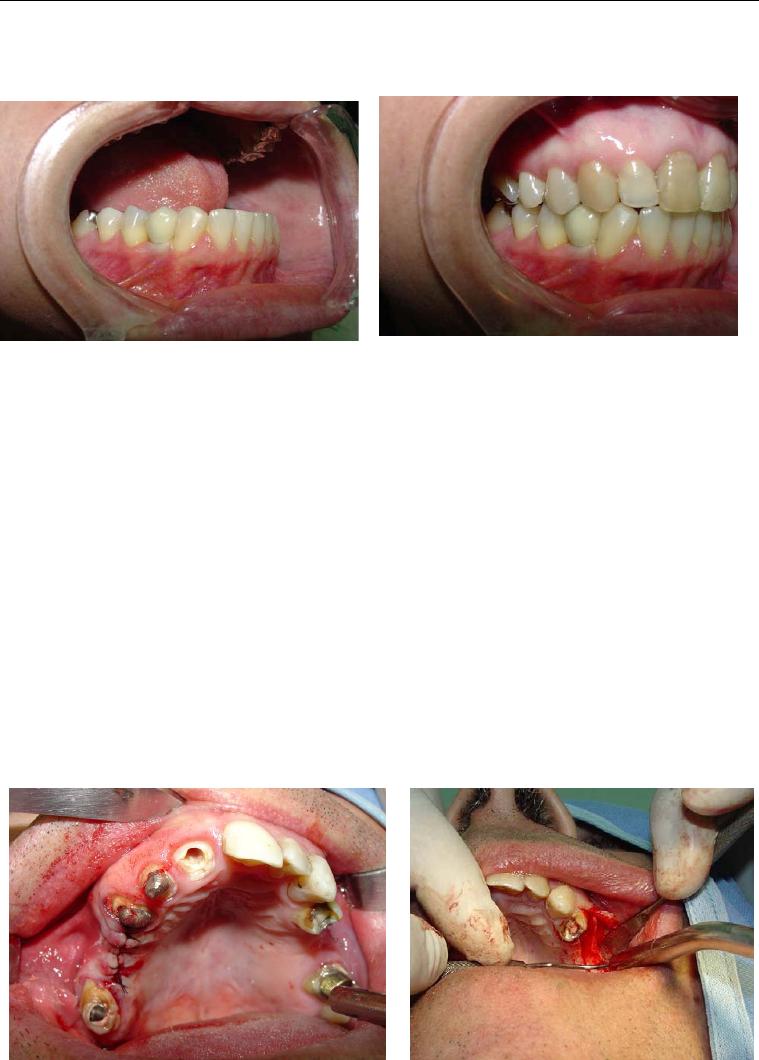

Foi no intuito de transpor estas dificuldades que se idealizou o sistema de

implante inicialmente conhecido como Wedge (figura 1) e que, após dez anos de